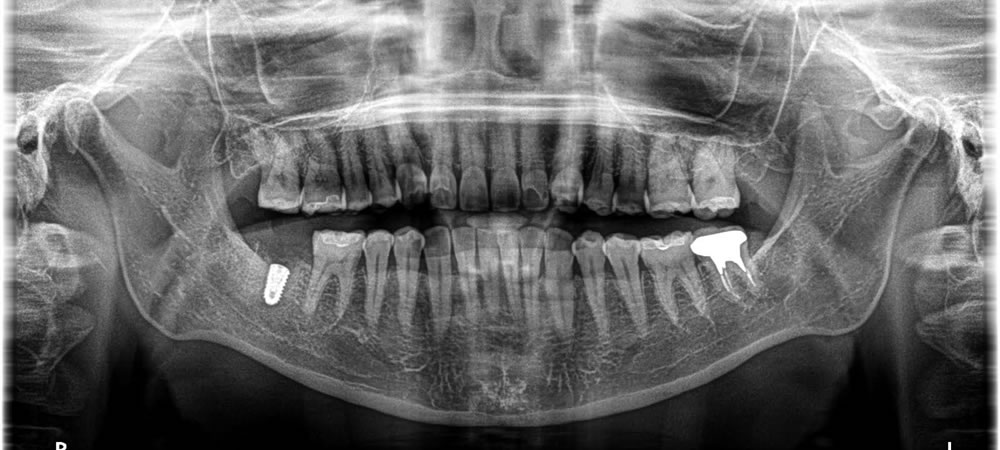

当該歯を抜歯してインプラントを埋入しました。

インプラント埋入時に骨造成(骨の再生を促す治療)を一緒に行いました。そこから4ヵ月待ち、上部にジルコニアの歯を装着して治療完了です。自身の歯と変わらない感覚でしっかり噛むことができるようになり、満足して頂くことができました。